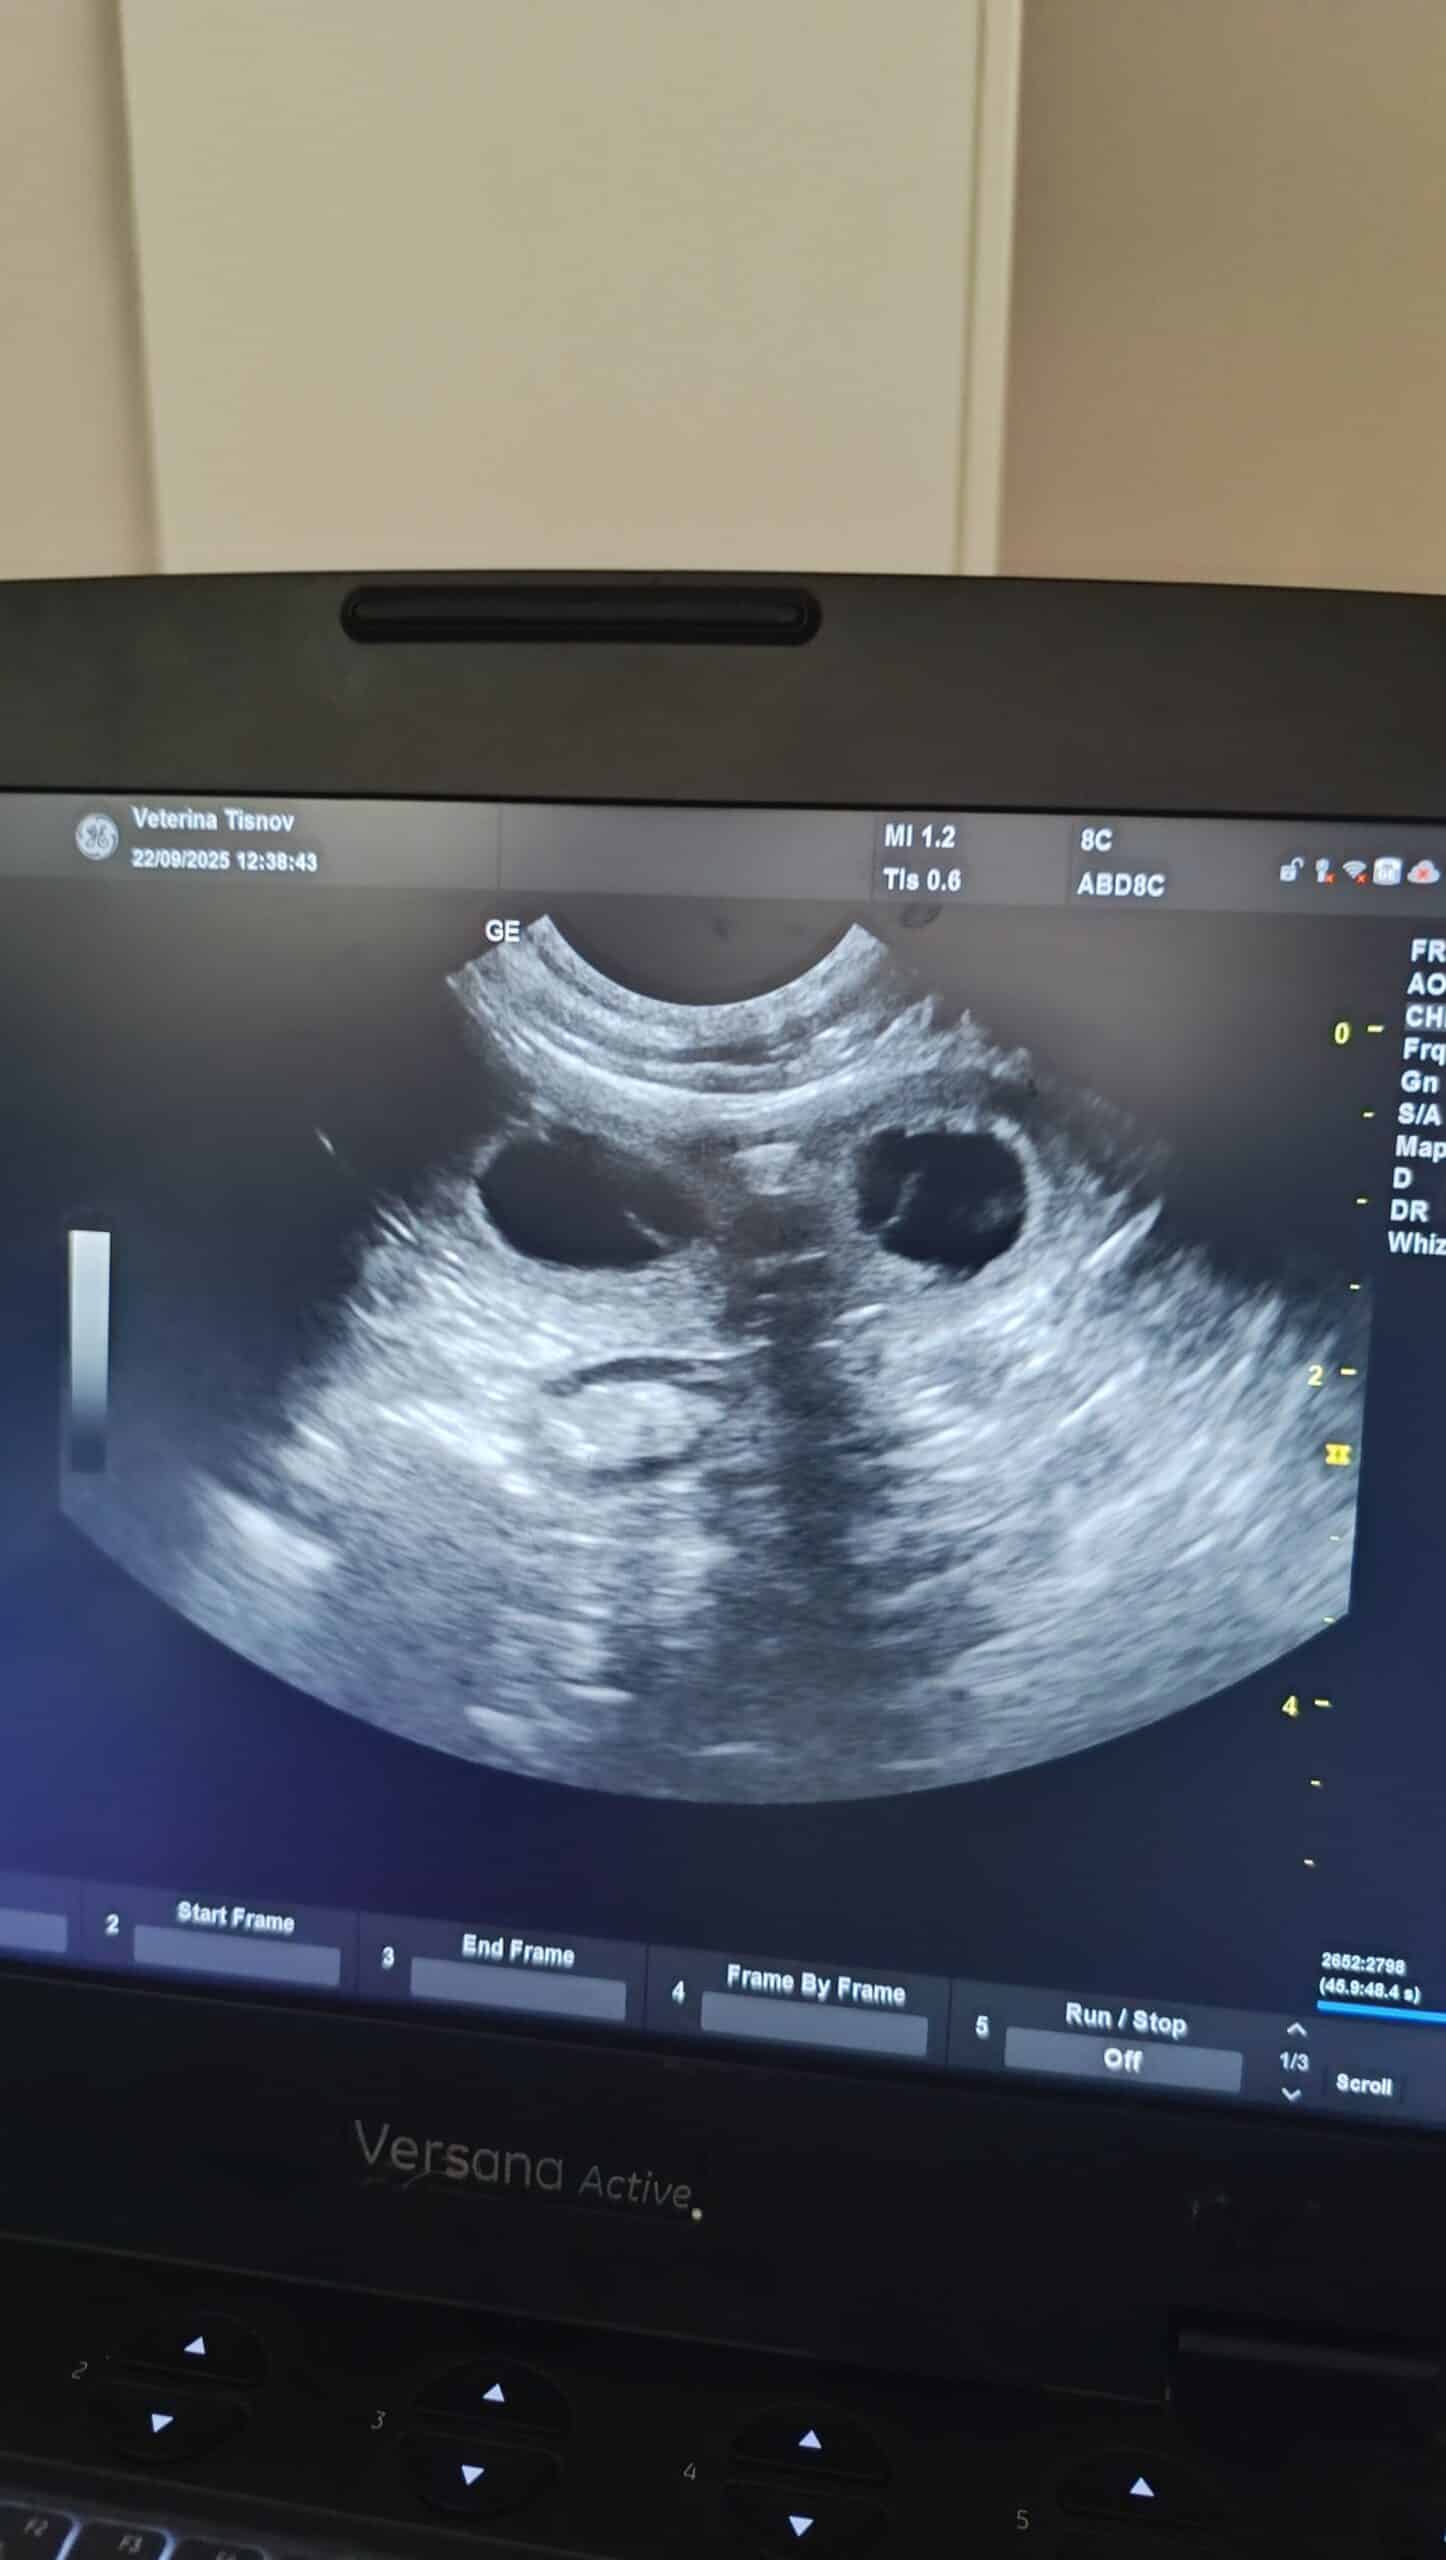

Šteniatka border kólie už túto jeseň 2025. Áno, je to tak. Sono dopadlo úspešne a ukázalo nám to, čo sme už všetci aj tak tušili. Maisynka je tehotná a krytie so Solom na konci augusta sa vydarilo. Na konci októbra/začiatkom novembra sa môžeme tešiť na malé guličky.

Maisynka sa má k svetu a tehotenstvo je na nej už vidieť.